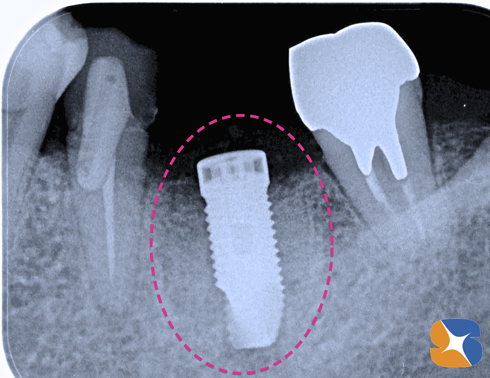

CT撮影での予測通り、ほっぺた側の骨を中心に大きく欠落していました。

この状況の中で、インプラントを的確な位置に、確実に植立します。

同時に、点滴中の患者様のルートより採血させていただきます。CGFと呼ばれる加工細胞を製造して、人工骨と混ぜ合わせ、再び顎骨を回復させていきます。

シュミレーション通り正確にインプラントを植立できました。あとは、骨の欠落部に、CGFと人工骨の一塊をやさしく添加すれば施術は完了です。

インプラントの周囲にCGFと絡めた一塊の人工骨を添加させます。この人工骨はやがて消失され、本物の骨に置き換わります。